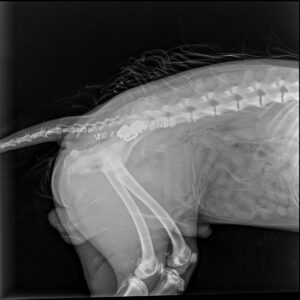

Kolejne zespolenie kości biodrowej po pojedynczej osteotomii miednicy – tym razem z zastosowaniem klamry kostnej w celu zwiększenia wytrzymałości.

Zachęcamy również do zapoznania się z naszą ofertą płytek do osteotomii miednicy – dostępne w systemie 2.4/2.7, 3.5 oraz 5.0!